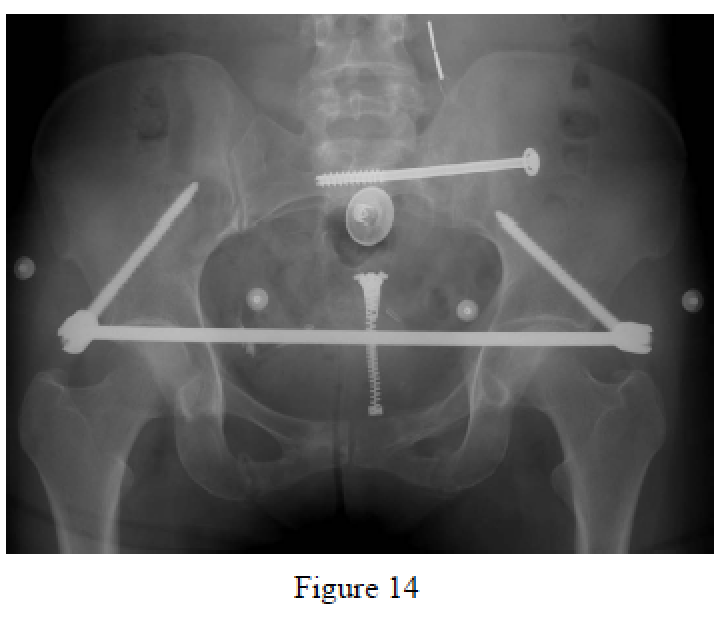

Vaidya R, Kubiak EN, Bergin PF, Dombroski DG, Critchlow RJ, Sethi A, Starr AJ. Complications of anterior subcutaneous internal fixation for unstable pelvis fracures: a multicentre study. Clin. Orthop Relat Res. 2012 Aug;470(8):2124-31. doi: 10.1007/s11999-011-2233-z. PubMed PMID: 22219004; PubMed Central PMCID: PMC3392373.